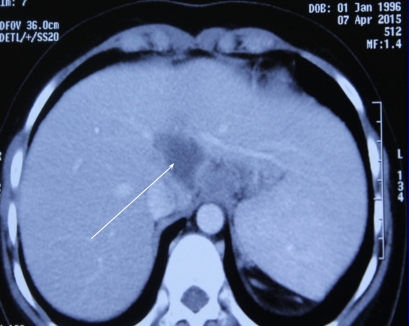

Bác sĩ Lê Hữu Phước, Khoa Nghiên cứu và điều trị viêm gan, Bệnh viện Chợ Rẫy, cho biết các bác sĩ vừa điều trị thành công ca lao gan trên nền bệnh rối loạn chuyển hóa đồng (bệnh Wilson) đầu tiên ở Việt Nam và là ca thứ 2 trên thế giới.

Thông qua các xét nghiệm về đột biến gen, nữ sinh được chẩn đoán bị bệnh Wilson. Sau 18 tháng điều trị, mọi thứ trong cơ thể Ngoan được trở lại bình thường, kể cả kinh nguyệt. Nhưng vài tháng sau đó, khi siêu âm bụng, các bác sĩ phát hiện một khối u ở gan đường kính 30 mm, do gan nghèo oxy, xảy ra trên cơ địa suy giảm miễn dịch.